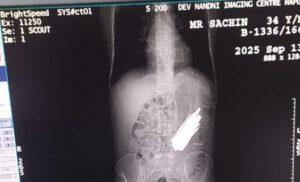

हापुड़(एजेंसी):उत्तर प्रदेश के हापुड़ जिले से एक हैरान करने वाली खबर सामने आई है। यहां एक मरीज के पेट से ऑपरेशन के दौरान 29 चम्मच निकली हैं। इतना ही नहीं 19 टूथब्रश व दो पेन भी निकले हैं।

बताया गया कि 40 वर्षीय सचिन बुलंदशहर का रहने वाला है और नशे का आदी है। वहीं, ऑपरेशन करने वाले चिकित्सक भी पेट में चम्मच और टूथब्रश देखकर हैरान रह गए। उसे नशा मुक्ति केंद्र में भर्ती था। वहां नशा न मिलने पर उसने यह सभी चीजें निगल लीं।

इसके कुछ समय बाद पेट में दर्द होने और तबीयत खराब होने पर उपचार कराया गया। पेट के अल्ट्रासाउंड व एक्सरे जांच कराने पर चिकित्सकों को जानकारी मिली थी। शहर के एक निजी अस्पताल में चार घंटे चले ऑपरेशन के बाद यह सब सामान निकाला गया।